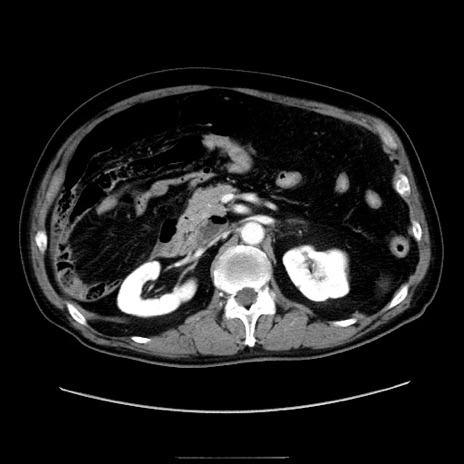

症例30(横断像)

【症例】80歳代男性

【主訴】臍周囲痛

【現病歴】約6時間前から臍下部痛が出現。次第に腹部膨隆・背部痛も生じてきたため来院。背部痛の場所は変化しない。

【既往歴】腎盂腎炎

【身体所見】意識清明、BT 36.3℃、BP  131/87mmHg、P 87bpm、SpO2 100%(RA)、臍周囲自発痛・圧痛あり、反跳痛なし、自発痛部位に一致して板状硬あり、腹部膨隆、腸雑音減弱、CVA tenderness両側陰性。

【データ】WBC 19600、CRP 0.33